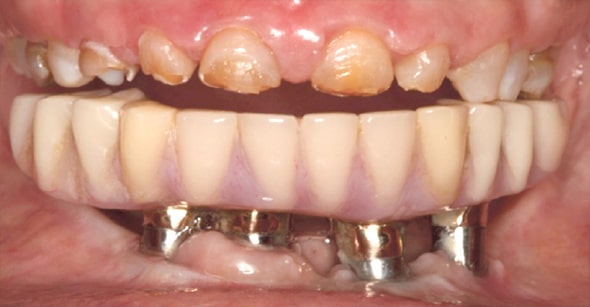

インプラントのトラブルでご来院された患者様の症例写真。インプラントを除去せざるを得ませんでした。